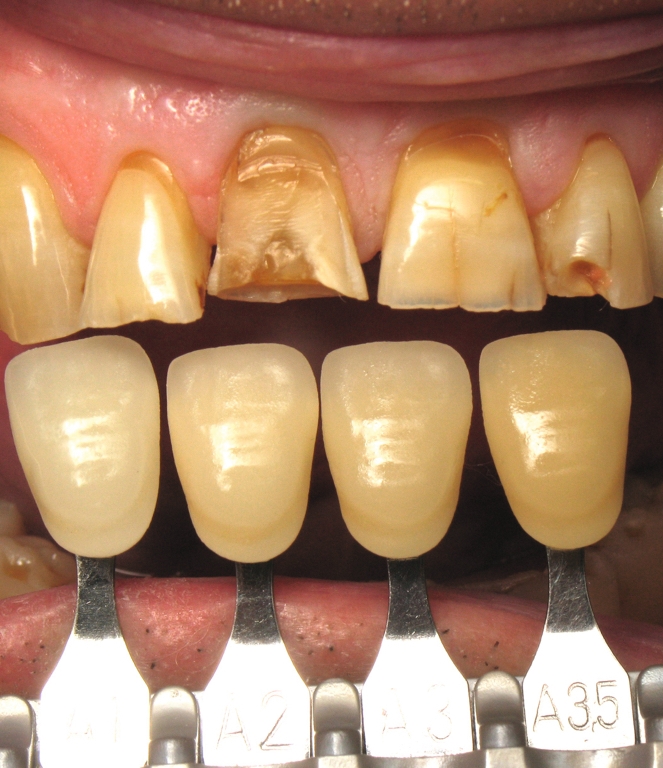

Une heure avant, la figure 10 montre un véritable patchwork de teinte dentaire. On constate une translucidité du bord libre, une saturation cervicale, des fêlures, des restaurations absentes, et une fracture coronaire complexe de la dent 11. Tous ces éléments ont amené les dents à réagir, en construisant au cours du temps, de la dentine réactionnelle a l’origine des nombreuses variations de teinte.

Dans le même temps, les figures 11 et 12 montrent la situation initiale de ce patient, venu en consultation pour la réhabilitation de ses incisives maxillaires. Le diagnostic a révélé un bruxisme nocturne à l’origine de plusieurs destructions coronaires : usure du bord libre, ab fraction, restaurations absentes, fêlures, et une fracture coronaire complexe. Il est aisé de comprendre pourquoi précédemment, le choix du matériau a été porte sur le zircone. Il est également facile de comprendre les motivations de ce patienta retrouver son sourire perdu. Cette dégradation par le temps est inéluctable, mais chez ce patient elle a été particulièrement rapide et agressive. Inverser le cours du temps est donc une évidence pour restaurer la santé dentaire de ce patient.

Fig. 10 : Teinte dentaire préopératoire.